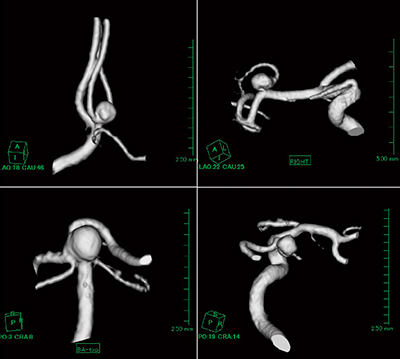

1.動脈瘤

頭部MRI検査では,動脈瘤のあるすべての患者のVR画像を作成する。年間の作成件数は約840件である。さらに,当院ではクモ膜下出血患者の約80%が脳血管撮影を行わず,MRAで動脈瘤の位置や形状を確認した後,手術となるため,日中や夜間の緊急などを問わず,それらのすべてにおいて動脈瘤のVR画像を作成している(図1)。

図1 MRA-VR画像(脳血管動脈瘤)